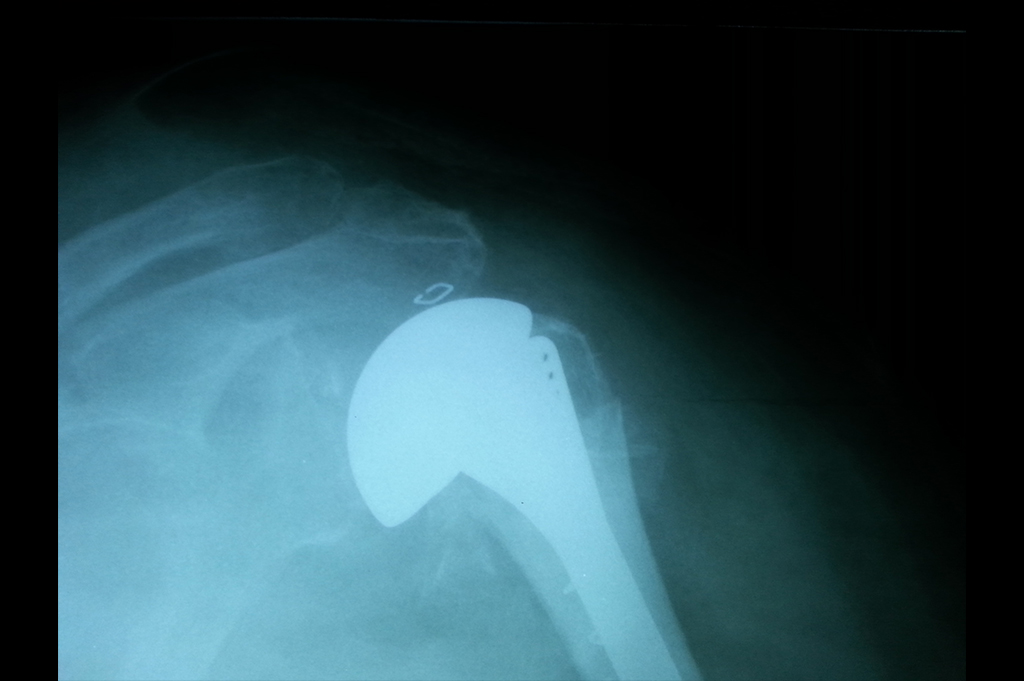

Shoulder Replacement